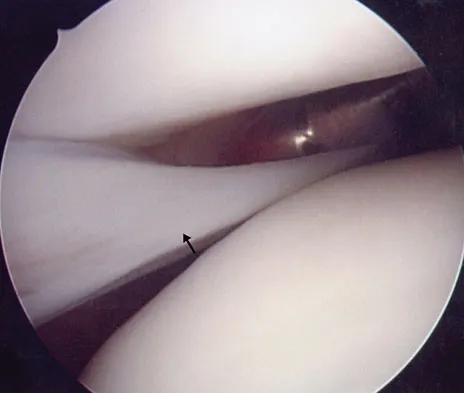

Management of a grade IV osteochondritis dissecans lesion of the capitellum should consist of

Osteochondritis dissecans of the capitellum is seen most commonly in adolescent athletes. It should be distinguished from osteochondrosis of the capitellum (Panner's disease), a self-limiting condition seen in younger patients. Lesions are graded I through V based on radiographic and arthroscopic appearance. Grade I lesions show intact but soft cartilage. Grade II lesions show fissuring of the overlying cartilage. Grade III lesions show exposed bone or an attached osteoarticular flap that is not loose. Grade IV lesions show a loose but nondisplaced osteoarticular flap. Grade V lesions show a displaced fragment. Simple excision of the loose osteoarticular flap is the treatment of choice for grade IV and V lesions. More complex procedures such as drilling of the in situ lesion, bone grafting, or internal fixation are associated with significantly worse results. While some authors advocate abrasion chondroplasty, the long-term benefits of the procedure are yet to be proven. Baumgarten TE: Osteochondritis dissecans of the capitellum. Sports Med Arthroscopy Rev 1995;3:219-223.